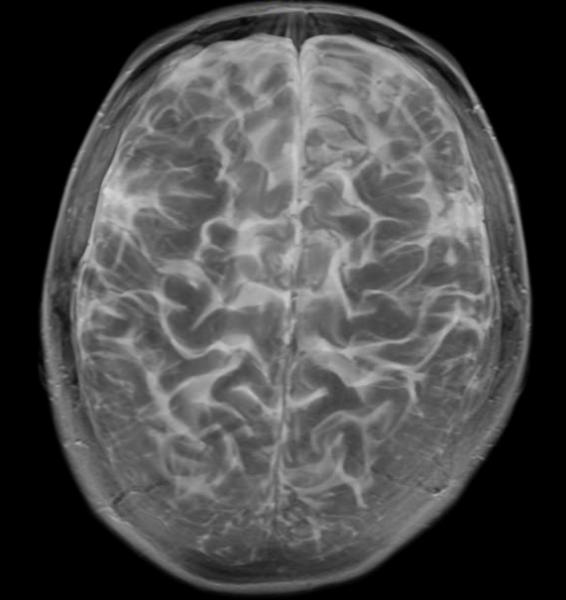

June 9, 2014 — After conducting a functional magnetic resonance imaging (fMRI) study on memory and categorization, researchers have shown for the first time that these mathematical models seem to correctly explain processing in the medial temporal lobes, a region of the brain associated with long-term memory that is disrupted by memory disorders like Alzheimer’s disease. The findings were published in The Journal of Neuroscience.